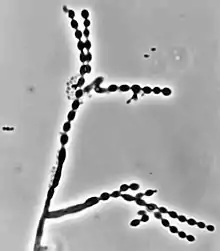

Cladophialophora carrionii is part of a group of melanized fungi, also known as “black yeasts” because its mycelial form has a dark green colour and its conidia have brown pigment.[2][6] Colonies grow at a modest rate on Sabouraud dextrose agar.[1] The conidia of C. carrionii are unicellular oval-shaped spores that are distinguishable due to the presence of two lightly pigmented scars.[6][7] Conidia vary in length (1.5-3.0 × 2.0-7.5 µm).[1] Its long conidiophores are similar to the genus Cladosporium, which comes from the Latin word "clado", meaning branched.[1] The genus Cladophialophora is distinguished from Cladosporium because in addition to chains of conidia, members of the genus Cladophialophora also produce phialides.[8] Cladophialophora carrionii is a dimorphic pathogen that changes states from a mycelial form to a muriform, yeast-like state once it invades its host.[3] Muriform cells are golden-brown in colour due to melanin deposition and have thick cell walls.[2][3]